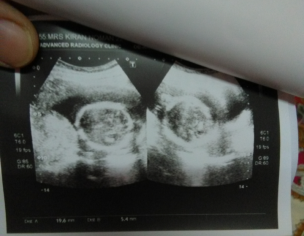

Yeh urine DR ki report ha kindly dakh kr bataen thek ha??

Thanks scan is ok you better have check up by gynacologist urine report is fine only few leakocytes take plenty of water